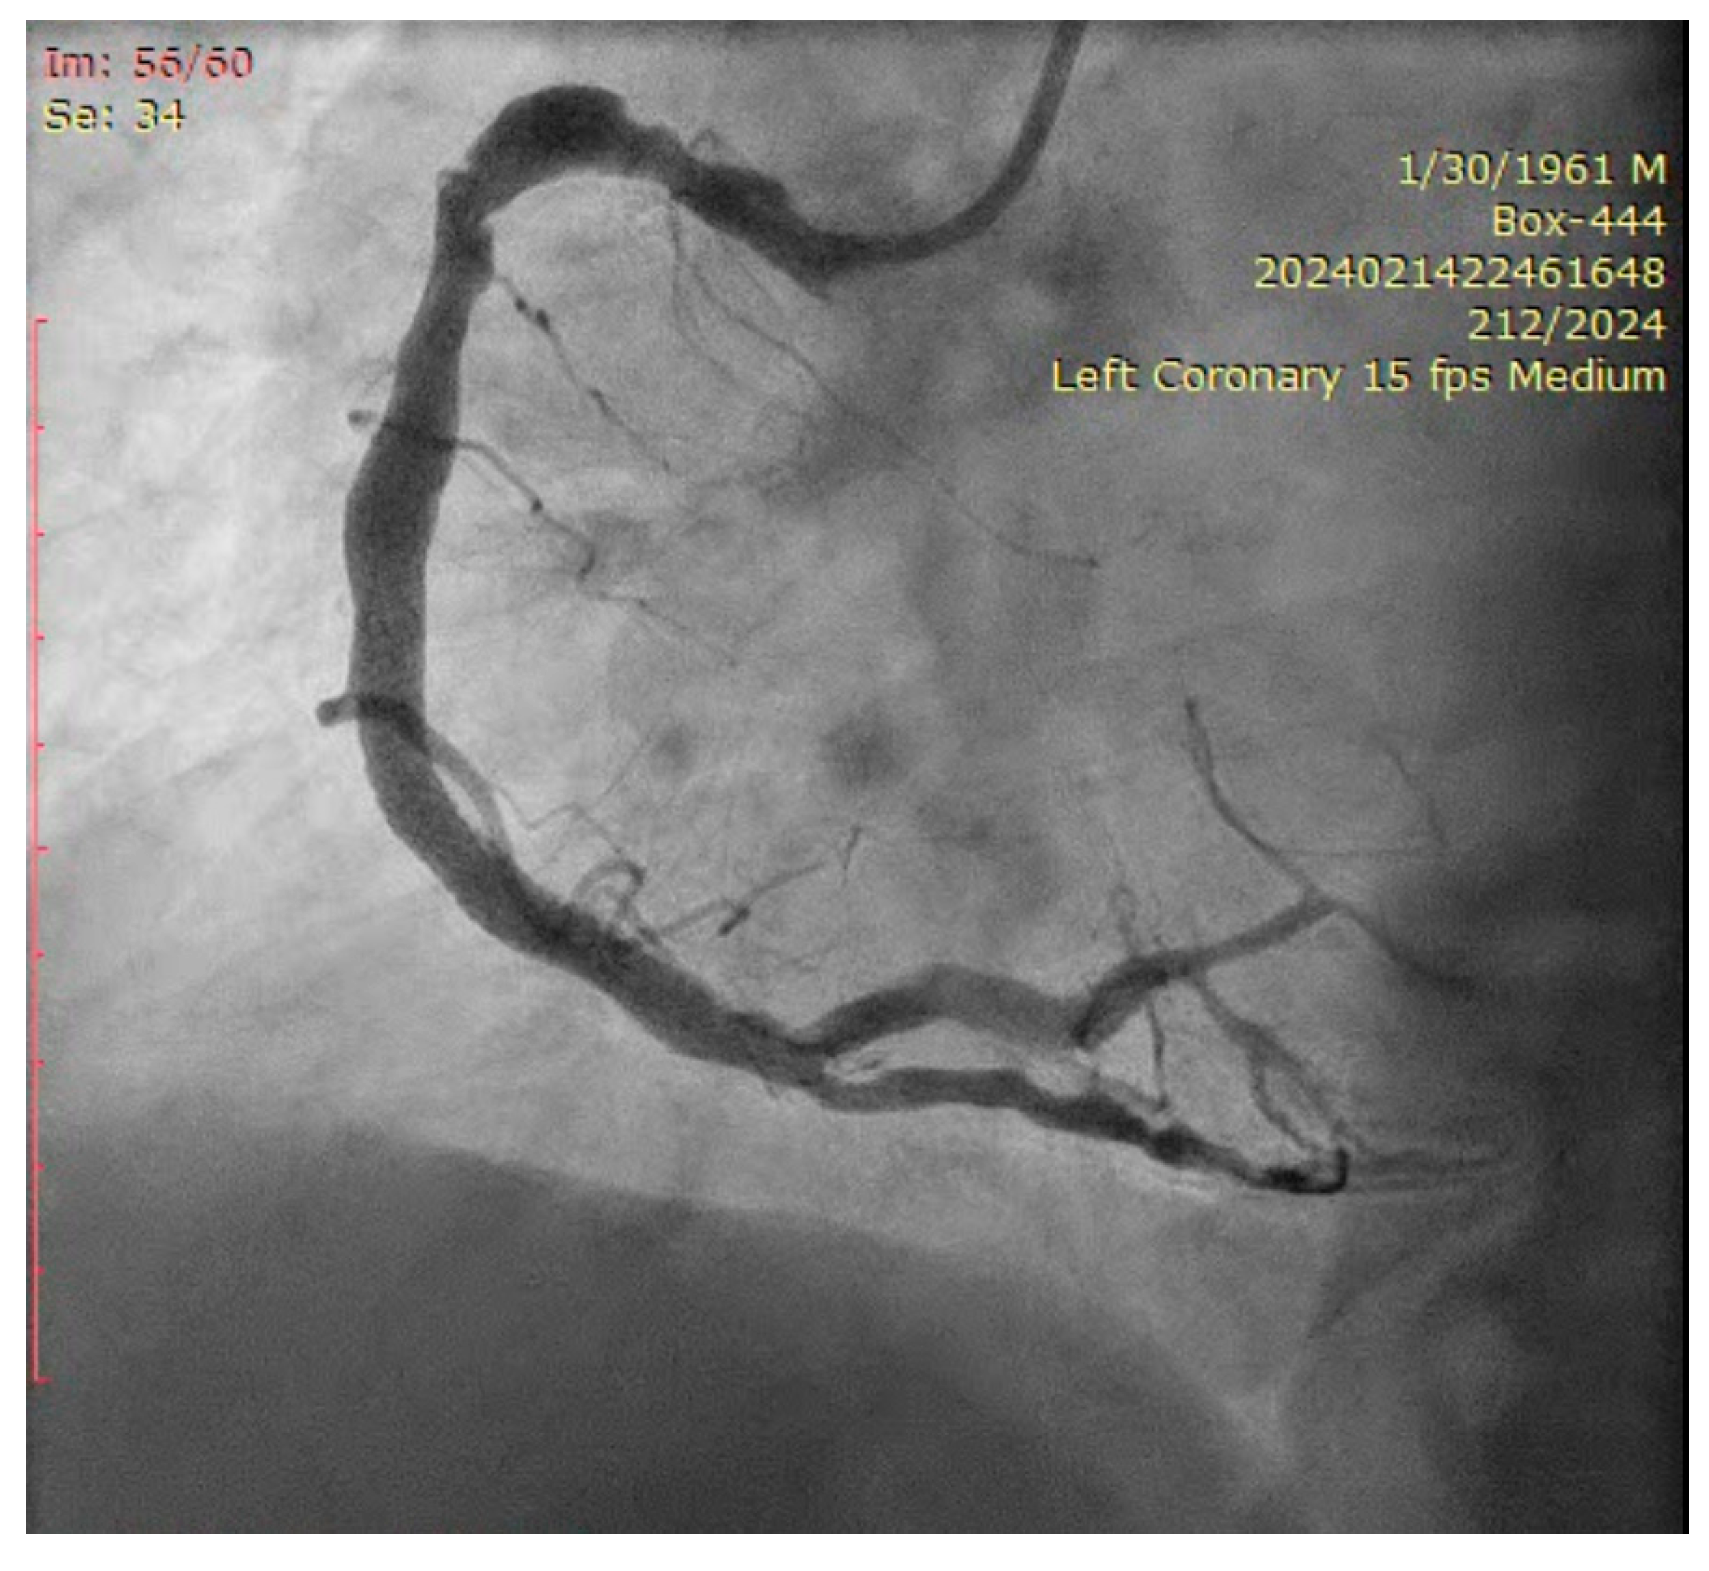

The ostium of left anterior descending artery (LAD) presented a 75% stenotic lesion, with the proximal segment displaying a 90% lesion (Figure 3). The left circumflex artery (LCX) revealed a 75% stenotic lesion of the ostium and tapered disease of its distal segment with areas of ectasic disease, with the ostium of the ramus intermedius (RI/RM) showing a 75% lesion (modified Medina classification 0-1-1-1 [4]) (Figure 4, Figure 5, Figure 6, Figure 7, Figure 8, Figure 9 and Figure 10).

Figure 4.

Left coronary artery—LAD and LCX (LAO caudal). Red arrow and circle—ostium of LAD. Yellow arrow and square—ostium of LCX.